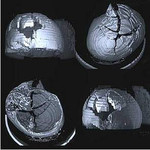

• Traumatologie

Fachübergreifend durch Teleradiologie

Die in der Dernbacher Klinik für Radiologie, Interventionelle Radiologie und Nuklearmedizin erstellten Bilder können per Teleradiologie über eine sicher verschlüsselte Datenleitung auf andere Rechner übertragen und befundet werden.

Dadurch können andere Fachabteilungen, wie beispielsweise die Neurochirurgie, bei der Diagnose und weiteren Behandlung fachübergreifend einbezogen werden. Eine Verlegung kann hierdurch oft vermieden werden, was gerade bei schwerverletzten oder schwerstkranken Patienten ein erhebliches Risiko darstellt.